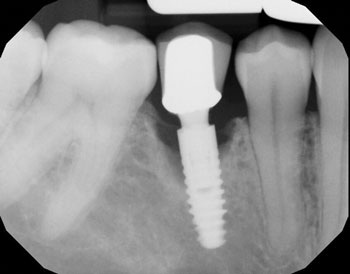

The following radiographs demonstrate representative surgical cases treated with a laser-assisted protocol, illustrating resolution of peri-implant radiolucency, stabilization of crestal bone levels and improved bone density patterns over time.

Fig. 2 depicts a dental implant at site #31 that presented with peri-implant probing depths of 12 mm on both the mesial and distal aspects, accompanied by suppuration. A 12-month follow-up radiograph reveals substantial peri-implant bone fill on both the mesial and distal aspects.

Fig. 2: Initial and follow-up radiographs of dental implant at site #31.